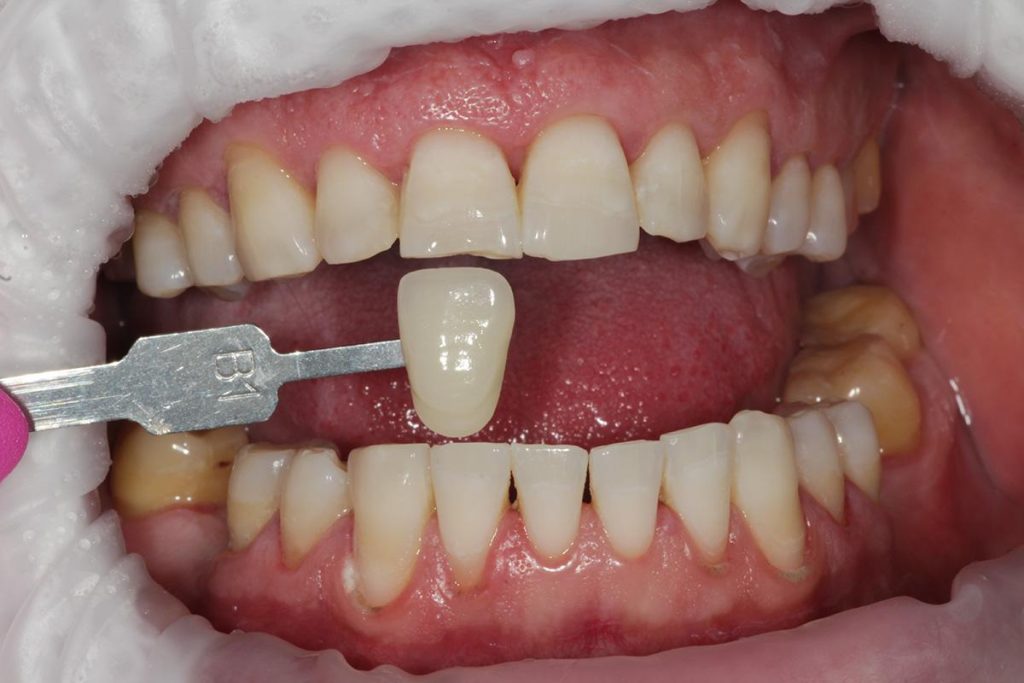

Aby osiągnąć taki efekt, musieliśmy przeprowadzić ekstrakcję złamanej górnej jedynki i w jej miejsce jednoczasowo wszczepić implant, a następnie na pozostałe zęby wykonać licówki i korony pełnoceramiczne w najjaśniejszym odcieniu.

Dobrze przeprowadzony zabieg implantacji natychmiastowej daje efekty jak na pozostałych zdjęciach! Na każdym etapie leczenia mamy pełną kontrolę nad wszystkimi aspektami przyszłej odbudowy protetycznej – można powiedzieć, że zachowujemy to, co najtrudneijsze do odtworzenia, czyli kształt dziąseł.

Cytując Michała Mokijewskiego: „Pacjent przychodzi po idealny ząb, a nie po implant”.

Tylko implantacja natychmiastowa pozwala nam uzyskać taki efekt w zaledwie 3 wizyty.